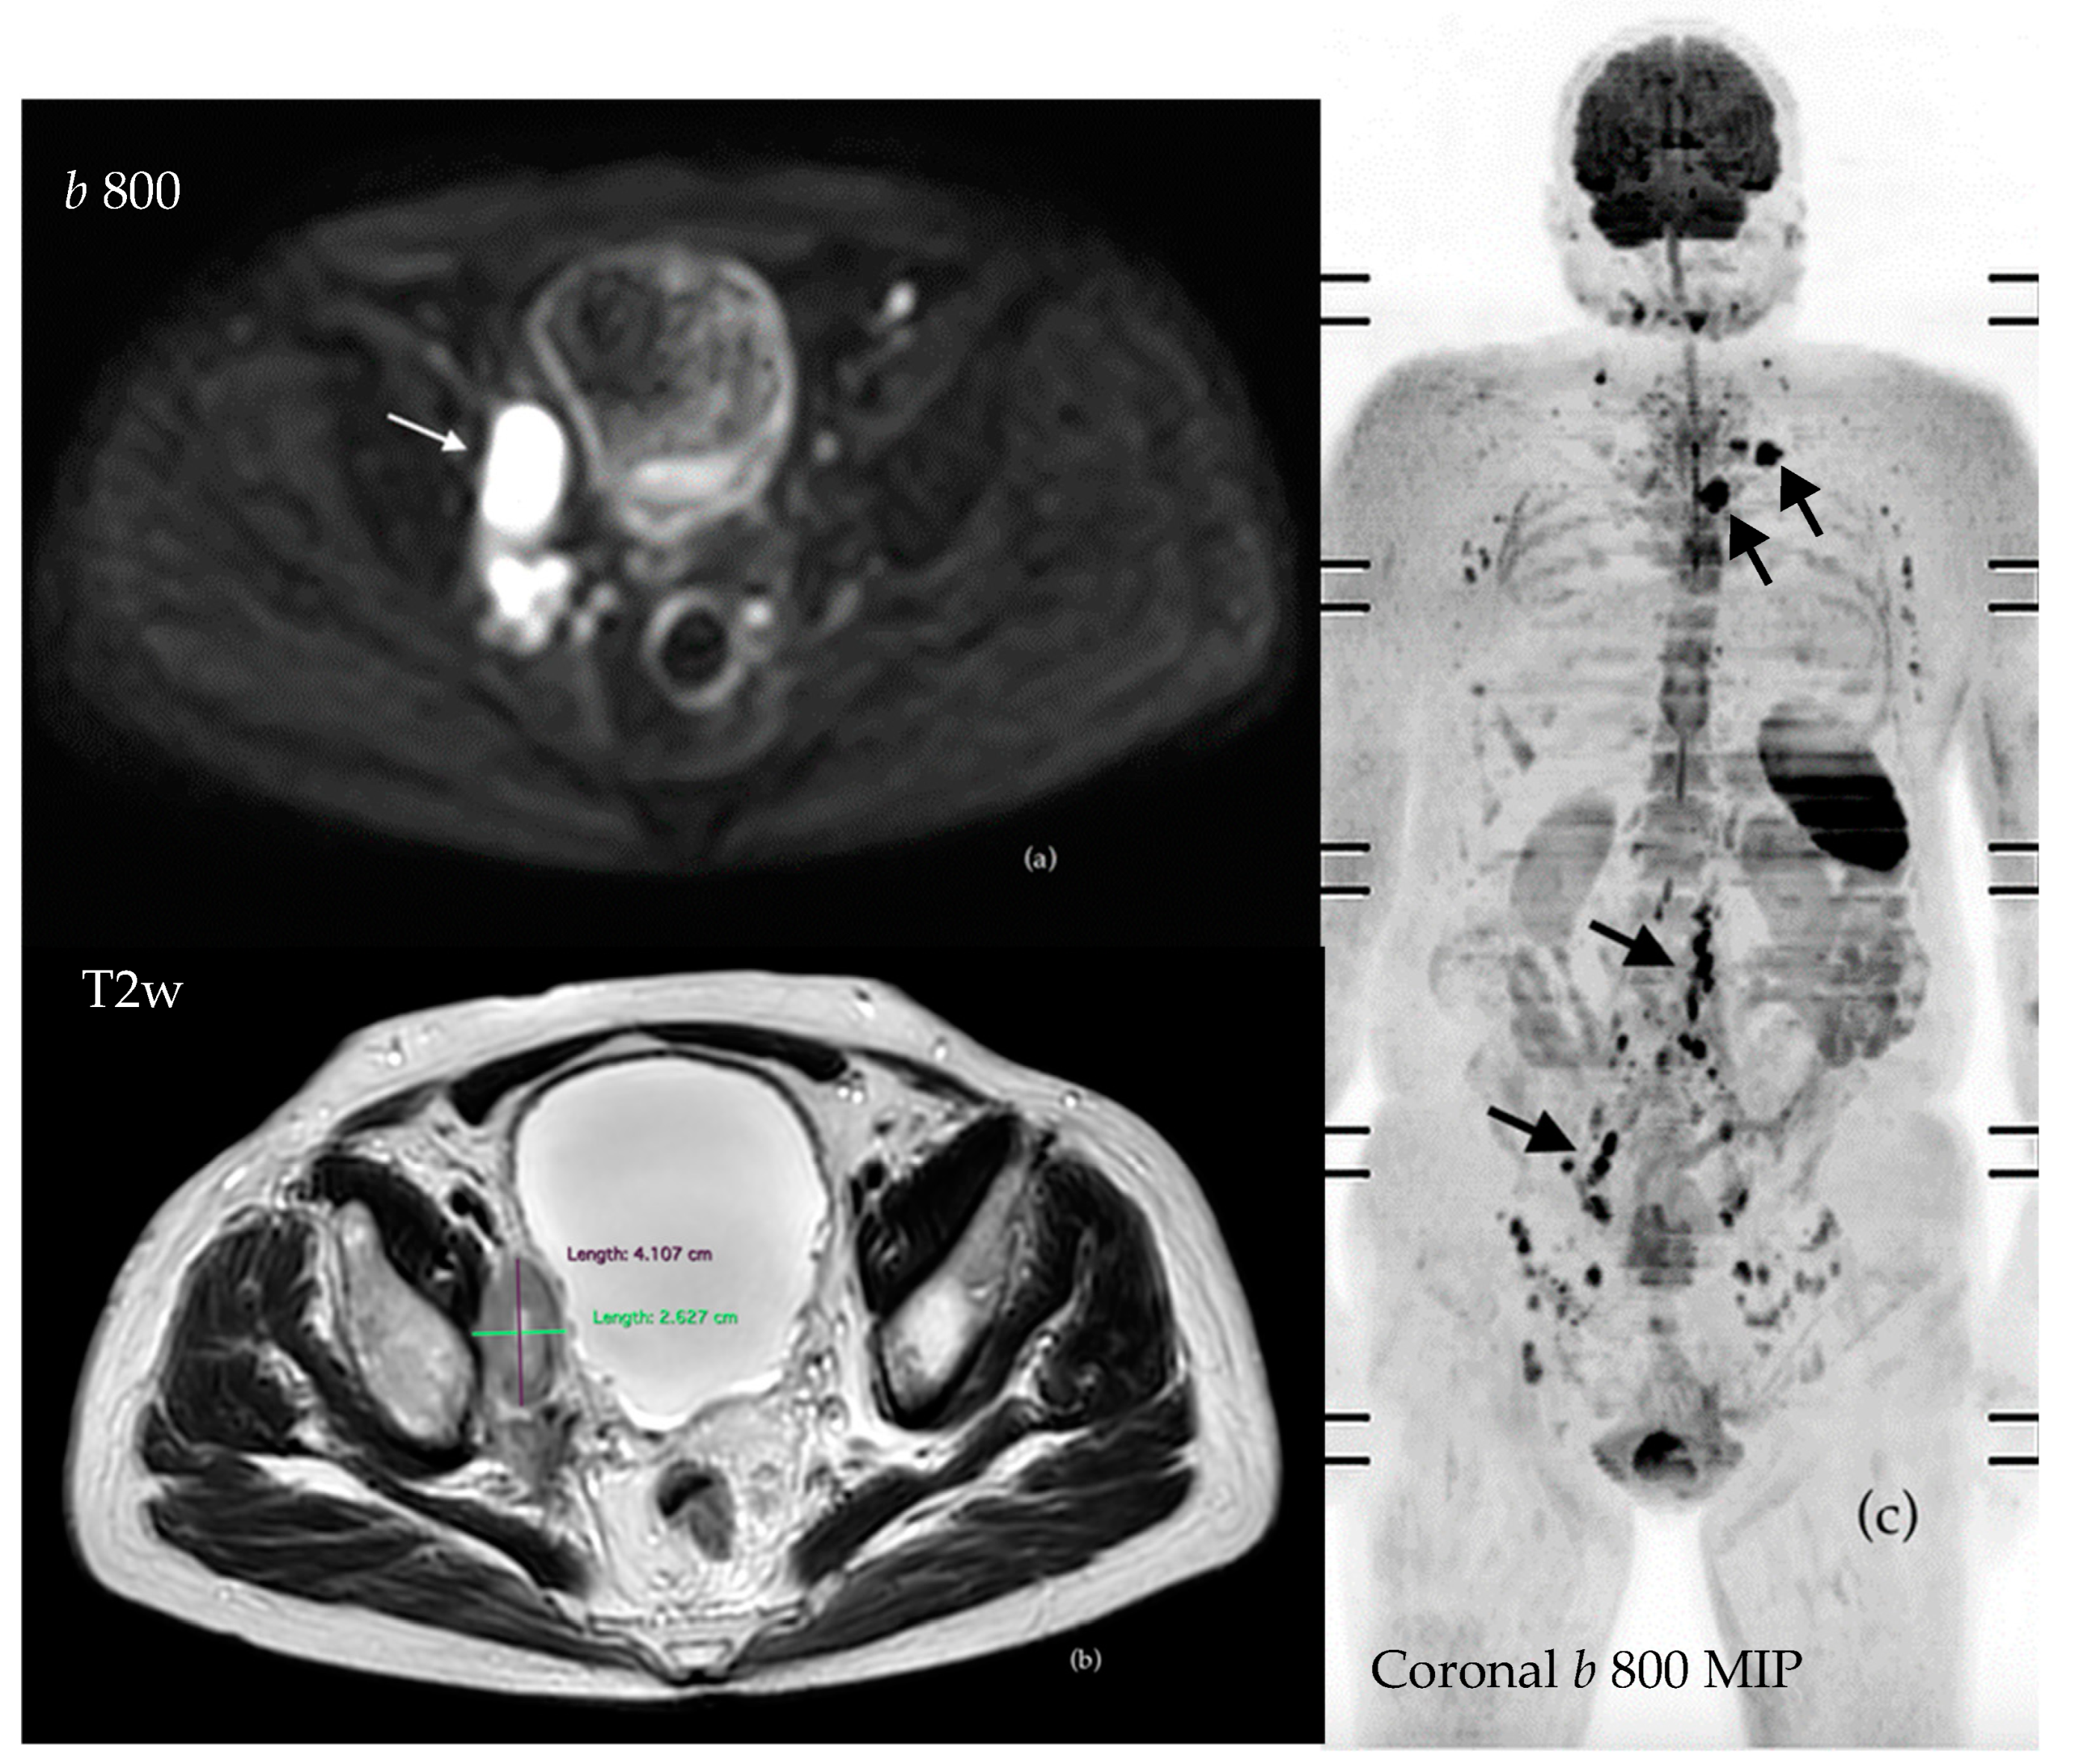

3.4.1. Evaluation of Bone Metastases with WB-MRI

3.4.2. Assessment of Nodal Disease

3.4.3. Assessment of Visceral Disease